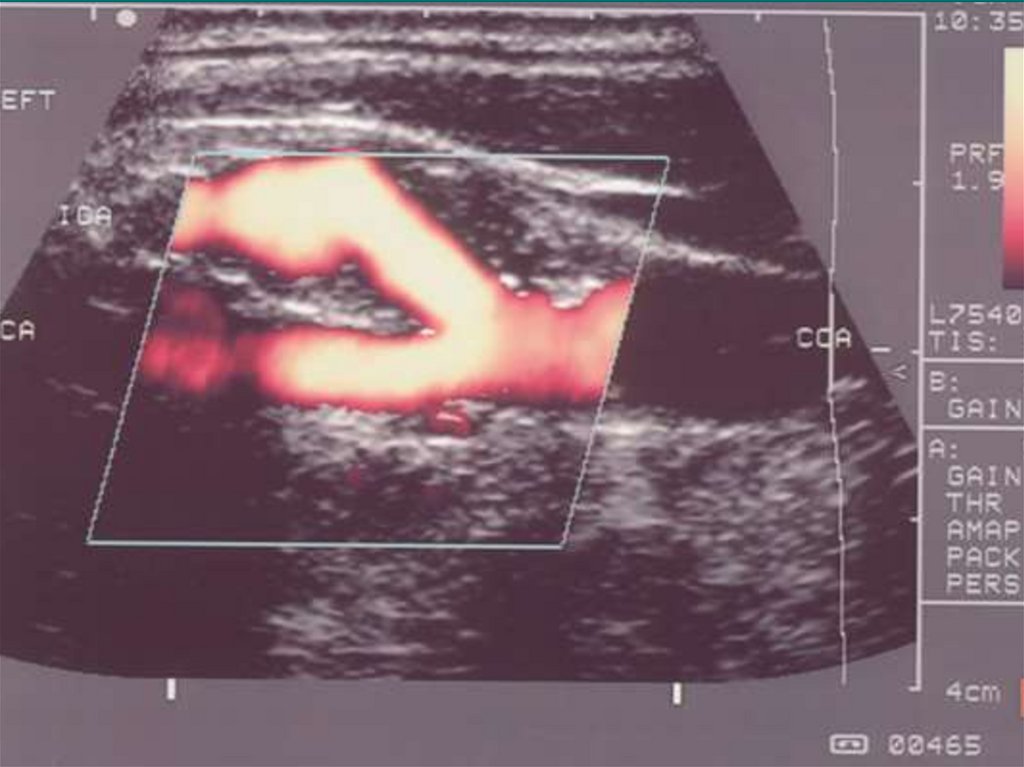

17. Ультразвуковая группа

• Эхоэнцефалография (ЭхоЭГ)

• Ультразвуковая допплерография (УЗДГ)

• Двойная ультразвуковая допплерография

• Транскраниальная допплерография

• Нейросонография